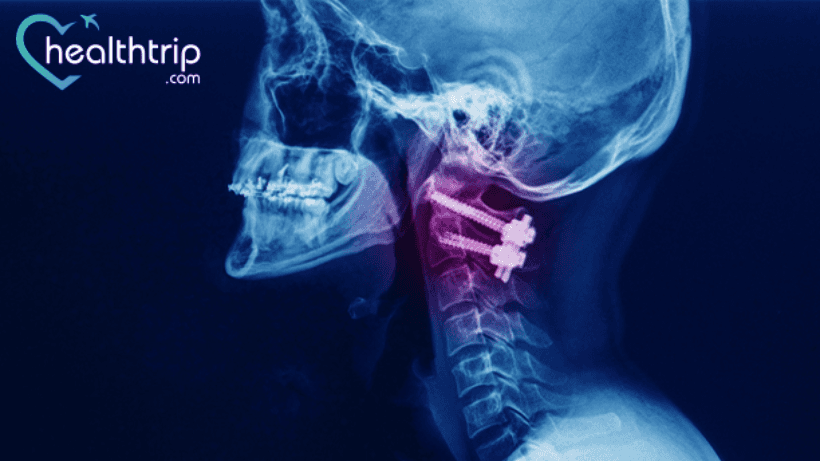

إحدى عمليات دمج العمود الفقري التي يتم إجراؤها بشكل شائع هي استئصال القرص العنقي الأمامي وجراحة الدمج (ACDF).

لقد كانت جراحة دمج عنق الرحم ناجحة جدًا للعديد من الأشخاص. الأشخاص الذين لم يحصلوا على نتيجة جيدة من الجراحة عانوا من زيادة آلام الرقبة وعدم استقرار الرقبة ونتوءات العظام. في بعض الحالات، تم إخطارهم أيضًا بأن هناك حاجة إلى مزيد من الدمج لإصلاح المشكلة الفاشلة.

وفقًا لخبرائنا في جراح العمود الفقري، فإن الأعراض التالية هي أعراض فشل جراحة دمج عنق الرحم: